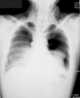

Bilateral tension pneumothorax

A pneumothorax is an abnormal collection of air in the pleural space between the lung and the chest wall. Symptoms typically include sudden onset of sharp, one-sided chest pain and shortness of breath. [Source: Wikipedia ]